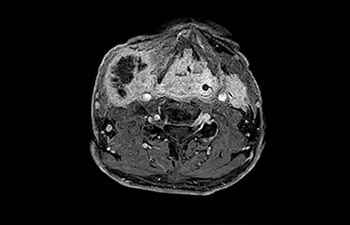

Cabeza y cuello

Lesiones de los ganglios linfáticos

con Compressed SENSE